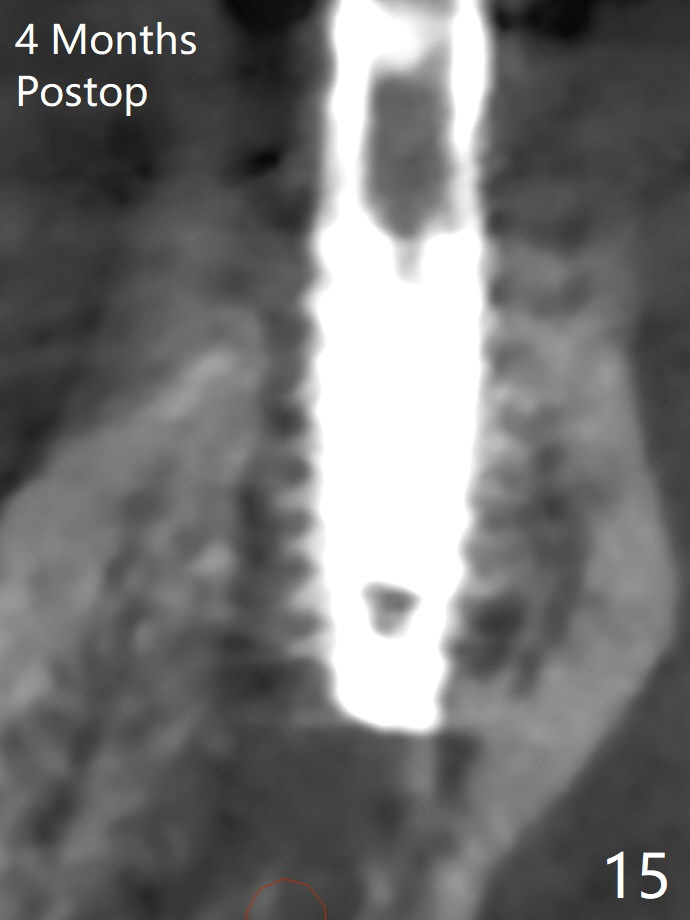

The extraction socket of #31 has a thin septum (Fig.2), which is removed partially with 12 mm bone trimmer (Fig.3). After placement of a 5x9 mm FC implant (~40 Ncm) and 6 mm bone profile drill, a 5.5x4(2) mm abutment is incompletely seated (Fig.5 <) and later is changed to a 4.5x1 mm temporary abutment (Fig.6, 8 T). The latter is used to fabricate a provisional, which in turn supports the distal papilla (Fig.8 *). The gingiva is slightly erythematous immediately post periodontal dressing removal (3 weeks postop, Fig.9). Take CT to confirm whether the cortical drill helps keep the #29 implant lingual. Use a profile drill at #29 if crestal bone loss is not obvious. There is bone coronal to #29 implant 4 months postop (Fig.10). Upon incision, the ridge is rounded (Fig.10'), but the implant appears to be buccally placed (Fig.10'' (post high speed handpiece and 5.5 mm profile drill)). The latter is confirmed by CT (Fig.12, as compared to design (Fig.11)). In spite of use of cortical drill coronally, the implant is still deviated buccally due to contrasting deferential bone density linguobuccally (Fig.13). By comparison, there is no such bone density differential involving an immediate implant at #31; the implant is placed in the socket without contacting the buccal or lingual cortices (Fig.14). The final implant is the same as expected (Fig.15). To avoid implant deviation in the lower premolar region, leave the root in place until osteotomy is finished. Five months postop, the temporary and healing abutments at #31 and 29 change to pair ones (Fig.16). Since there is limited clearance from the crestal bone, smaller abutments are used with the apparently same degree of seating (Fig.17). The abutments are prepared due to the mesial (#31) and buccal (29) tilt before impression.